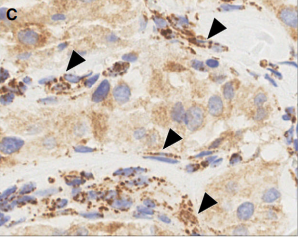

- SDHB标记: SDHA/B/C/D/AF2基因(统称SDHx)的突变或甲基化均可导致SDHB蛋白表达异常(缺失或减弱)。SDHB表达异常提示可能存在SDH缺陷相关的遗传性肿瘤综合征。本例患者SDHB蛋白表达正常。

SDHB免疫组化结果判读示例:A图为正常表达(胞浆颗粒状强阳性),B-F图均为不同模式的表达异常 [引自PMID:35546442]